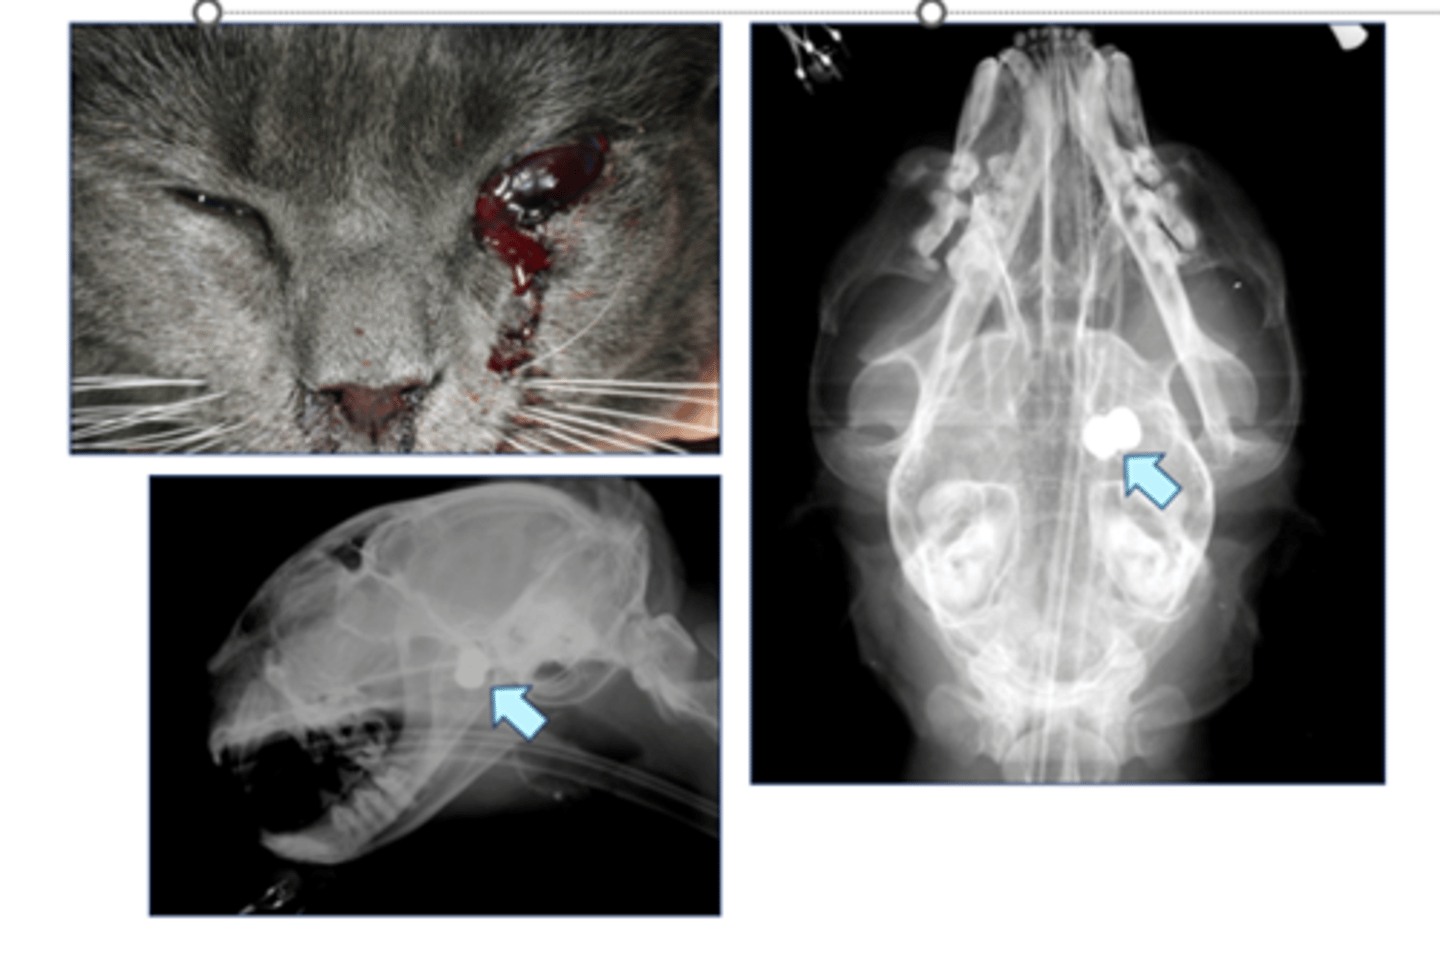

Cat shot in eye by airgun pellet